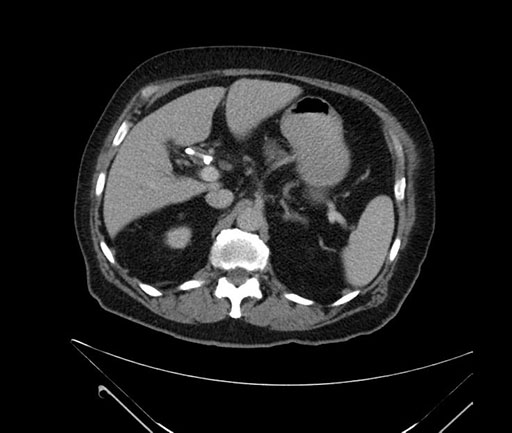

Whipple (pancreaticoduodenectomy) [case 7]

Imaging Analysis

Look through the patient's CT scan to identify any areas of concern for the necessary procedure.

Based on your CT findings, which issue(s) would give reason for "planned slowing down moment(s)" in this case?

Considering a standard Whipple procedure, what step(s) of the operation would you do differently in this case?